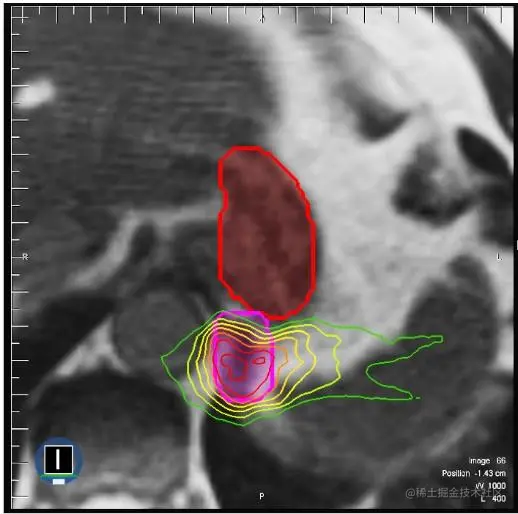

可视化

上面的肿瘤(粉红色粗线)靠近胃(红色粗线)。 高剂量的放射线直接照射到肿瘤上,同时避开胃部。 剂量水平用颜色表示。 较高剂量用红色表示,较低剂量用绿色表示。\